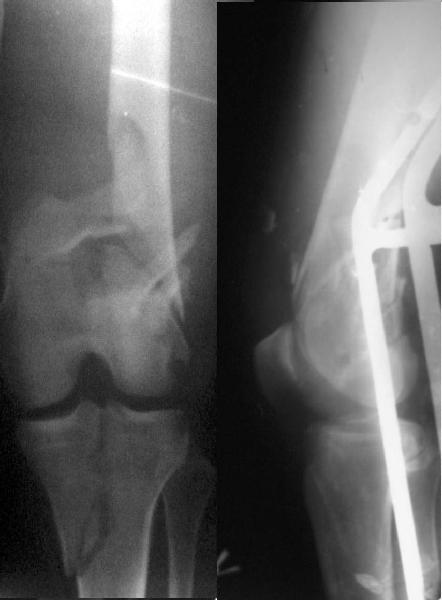

This is what we have done... As generally true for LISS look at the bone not the hardware.

There are two more srews above. The one not completely in got damaged head.

Look what we would have done.